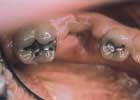

Inlay

before

after